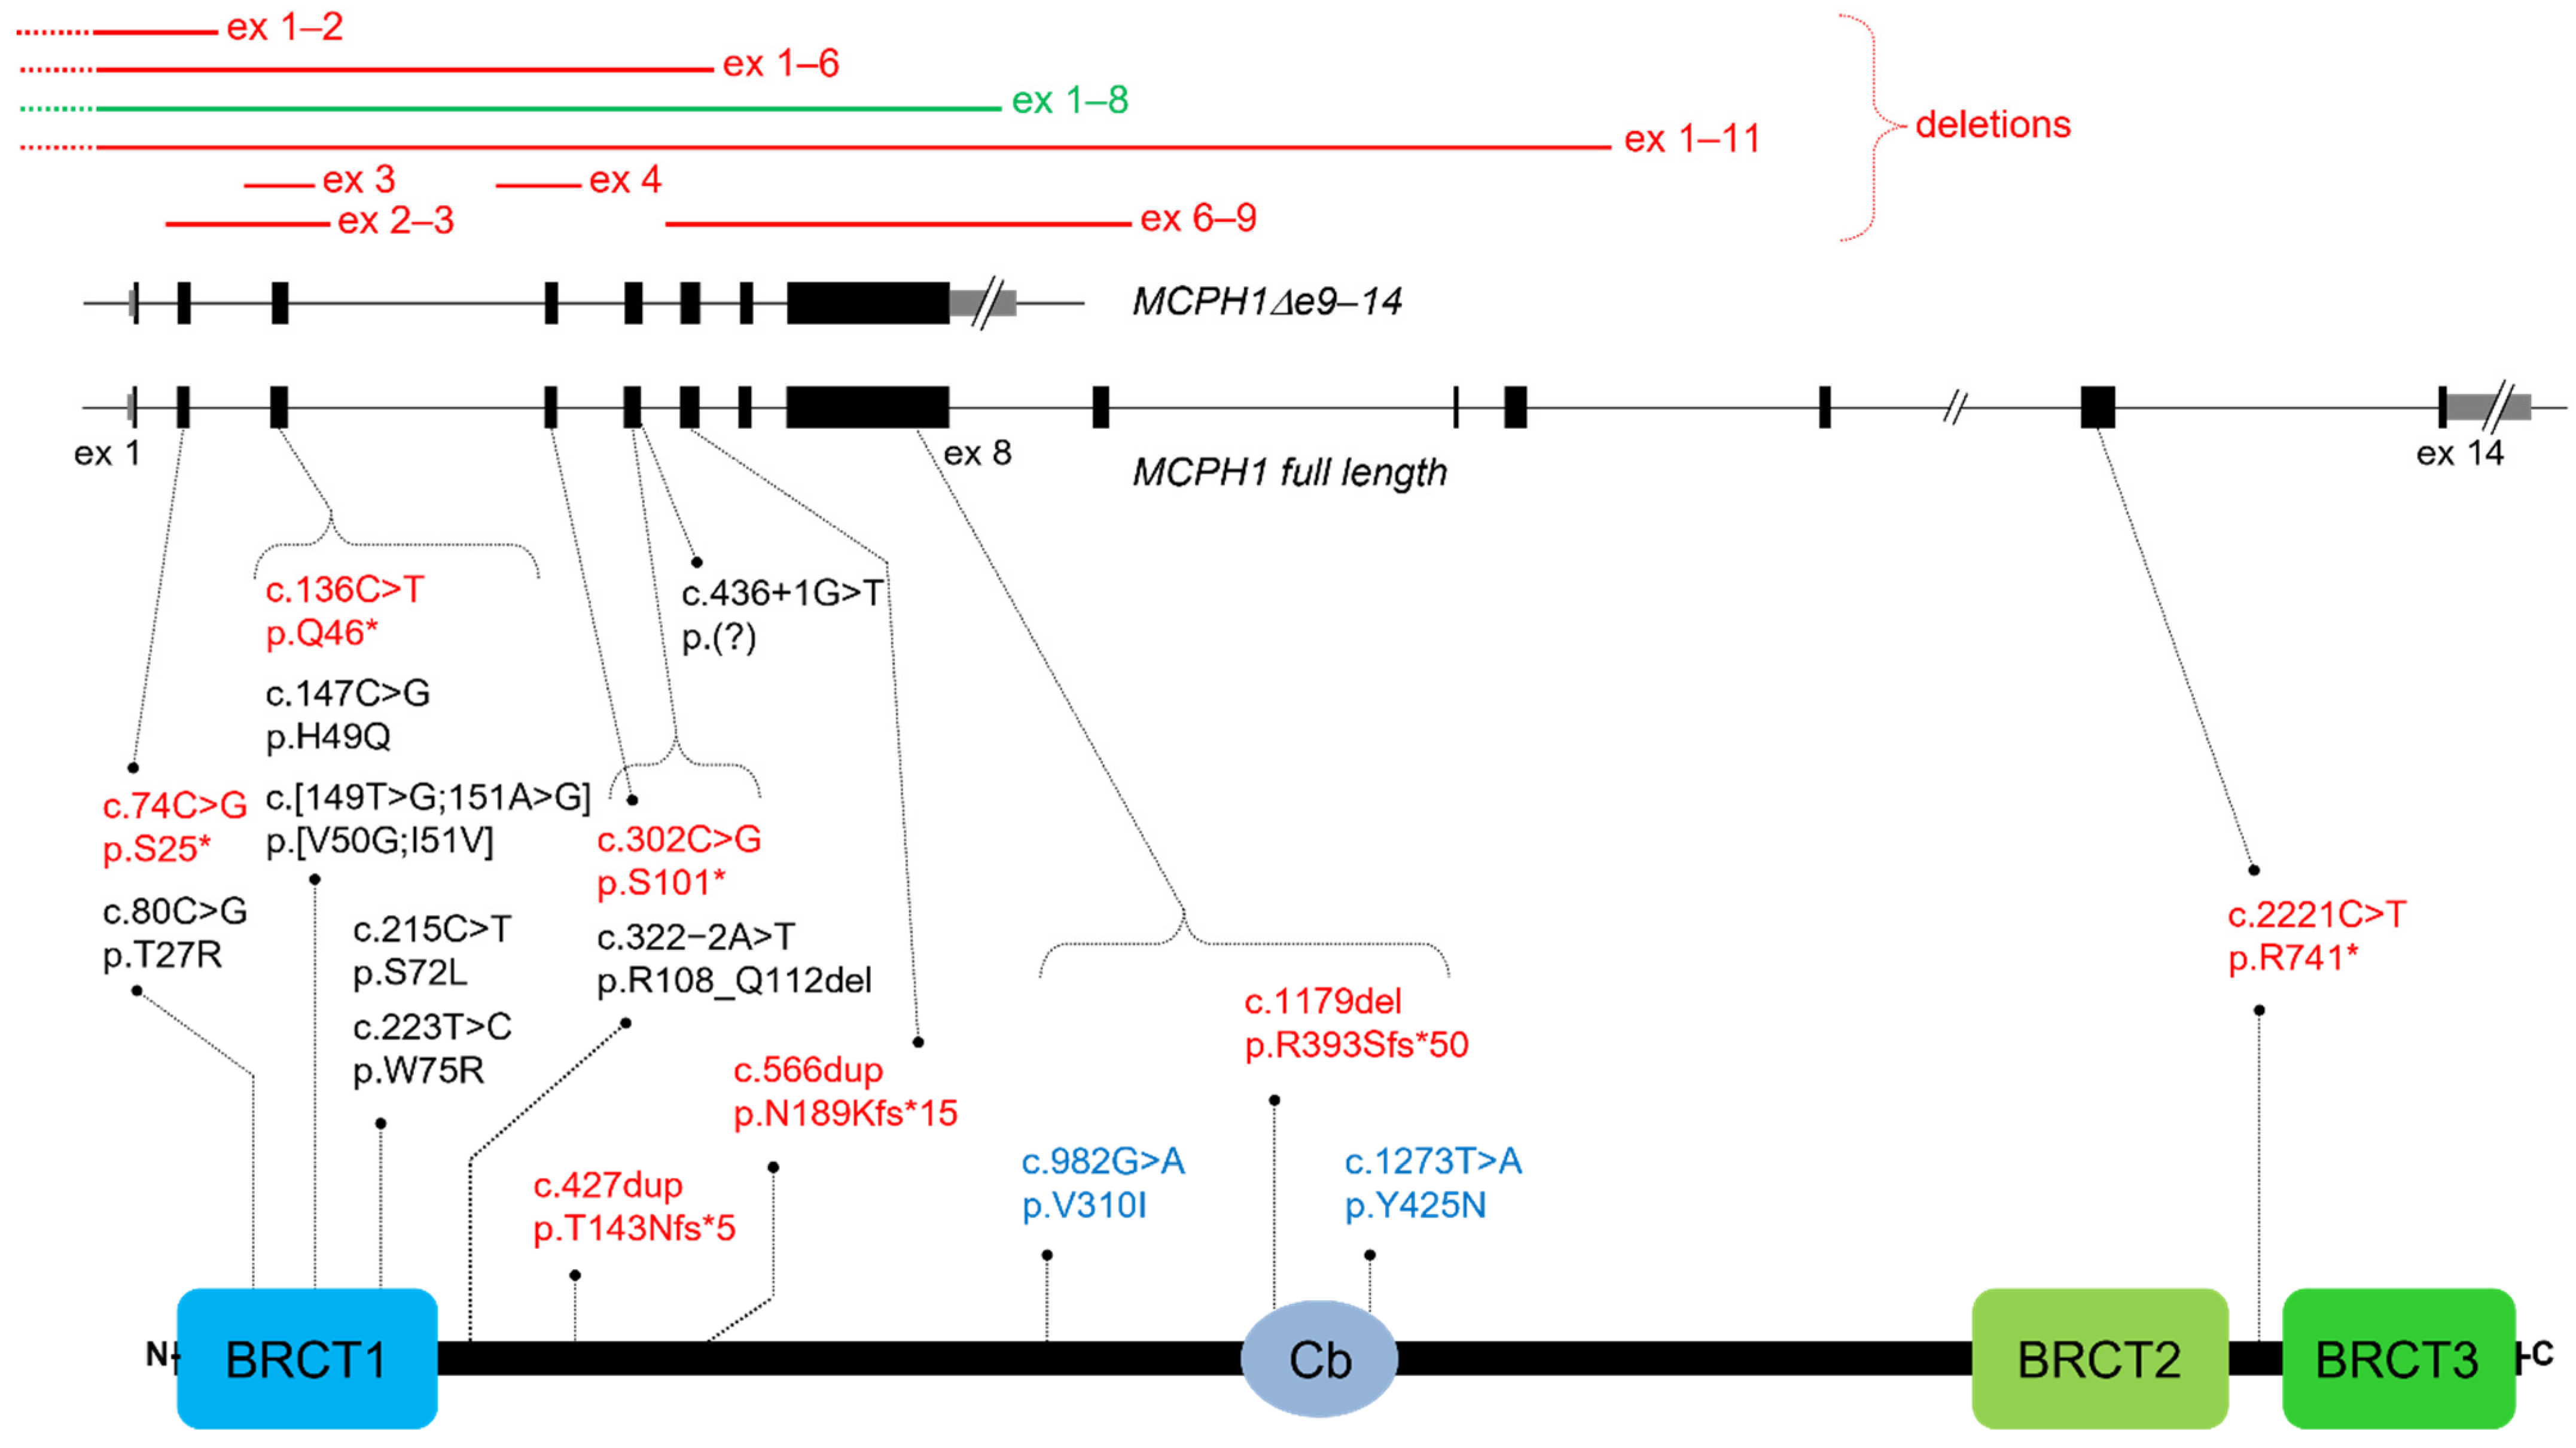

2.2. Molecular Diagnosis